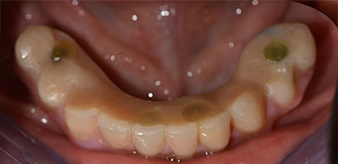

Направи се скенер с триизмерна компютърна томография (CBCT, Planmeca), за да се подпомогне планирането и да се намалят рисковете. Той показа, че качеството и количеството на наличната кост са достатъчни за операцията и имедиатното възстановяване, използвайки Fast & Fixed метод. Следвайки протокола за тази концепция, имплантите са поставени на 35, 32, 42 и 45 позиция. Ангулирането на дисталните импланти до 45° промени профила в задната зона и осигури по-голяма поддръжка в многоъгълната зона (Фиг. 3).